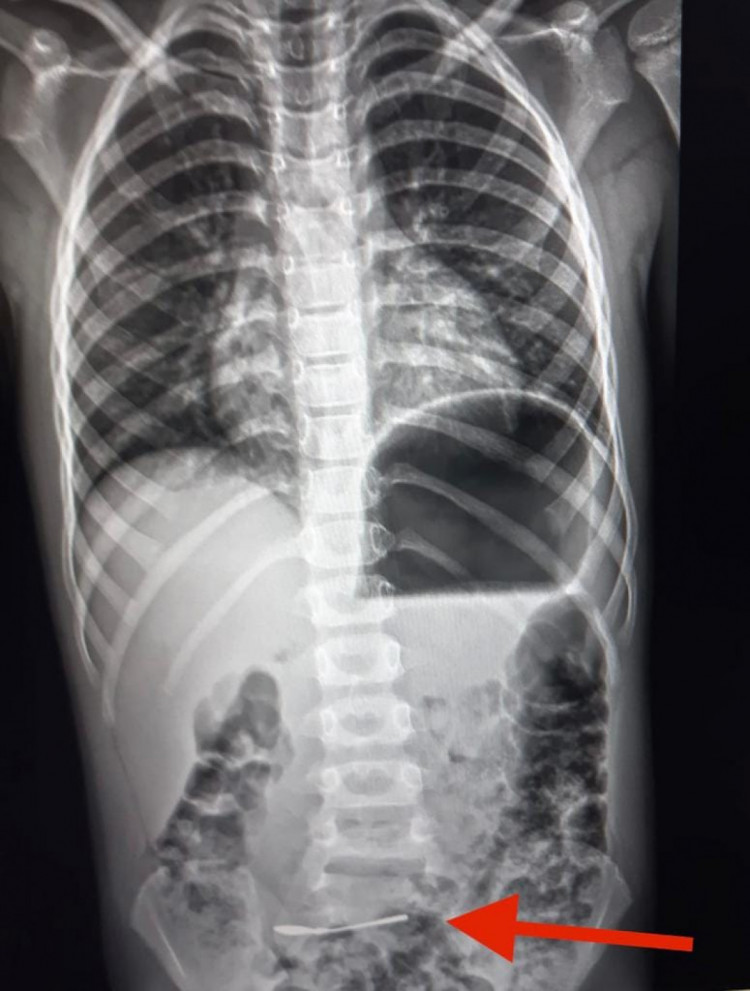

Ребенок проглотил ложку в Харькове (коллаж РБК-Украина)

В Харькове госпитализировали 6-летнего ребенка, который проглотил ложку. Врачи маленького пациента обследовали и решили наблюдать.

Так, в Харькове в областную детскую клиническую больницу доставили 6-летнего ребенка с серебряной ложкой в кишечнике.